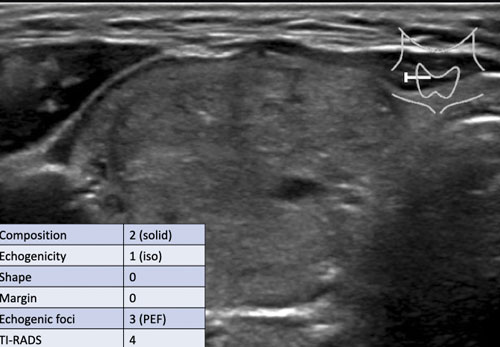

Trường hợp 3

Quan sát hình ảnh và xác định điểm TI-RADS.

Cuộn hình ảnh để xem điểm TI-RADS.

Lưu ý các tiêu điểm tăng âm nhỏ hiện diện.

Tổng cộng 6 điểm tương ứng với điểm TI-RADS là 4.